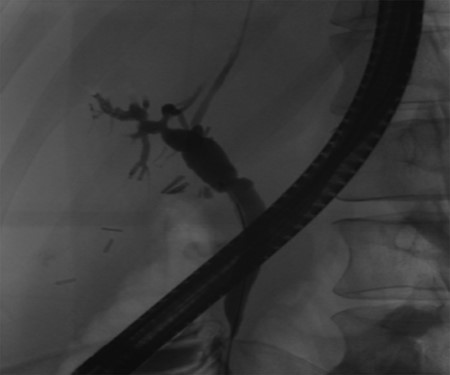

Independent biliary duct (blue arrow) draining to the cyst and not to the liver parenchyma.

A 35-year-old female with a medical history significant for acute biliary pancreatitis status post laparoscopic cholecystectomy, presented to the surgery clinic as a new consult for a large cystic liver mass with increasing abdominal pain for 2 weeks. Patient reported suffering from severe pain in right chest, shoulder and diffuse abdominally that worsened with standing. Patient complained of inability to inspire due to pain and a 10-pound weight gain over 2 months. She confirmed decreased appetite especially with solids, nausea and emesis, alternating constipation and diarrhea, bruising, and pruritus at night. Computed tomography (CT) scan demonstrated a peripherally septated 10 x 7 cm cystic mass in the liver with intrahepatic biliary dilation (Fig. 1). The patient was referred for endoscopic retrograde cholangiopancreatography (ERCP) to establish preoperative biliary anatomy and was found to have moderate compression of the common hepatic duct managed with a right hepatic biliary endoprosthesis (Fig. 2); no obvious communication of the biliary tree with the cystic lesion was seen. Patient symptoms persisted despite optimizing with a protein-rich liquid diet; thus, the decision was made to proceed with the surgical plan for an open partial central hepatectomy. The patient was taken to the operative theater. After induction of general anesthetic, an upper midline incision was made. Inspection of the abdomen and liver showed no metastatic lesions grossly or with ultrasonographic imaging. The cyst was visible upon entry into the abdomen with no solid component to the mass in proximity to the cystic neoplasm. The second portion of the duodenum was adherent to the cyst with inflammatory adhesions and was quite boggy. A partial central hepatectomy was performed; a 3 mm biliary duct was found communicating to the cyst only with no drainage to the minimal liver parenchyma that was removed (Fig. 3). The cyst was resected en-bloc and was sent for permanent section (Fig. 4), which diagnosed the tumor as a low-grade mucinous cystic neoplasm measuring 8.5 × 7.2 × 6.4 cm. Microscopy revealed a smooth-walled, multiloculated cyst filled with a yellow-golden, semi-transparent and mucinous fluid (Fig. 5a–c). The cyst was lined by a mucinous epithelium with ovarian-type stroma. No high-grade dysplasia or malignancy was identified. The postoperative course was uneventful, and the patient was discharged on postoperative day 6. At the 4-week postoperative visit, the patient was healing well with some incisional soreness; patient was seen for removal of her biliary endoprosthesis, and ERCP found left sided intrahepatic duct biliary dilatation including a small biliary fistula from the left system (Fig. 6) with the appearance of torque on the extrahepatic biliary tree. A biliary endoprosthesis was left in place, and the patient returned for repeat ERCP 4 weeks later with resolution of all findings (Fig. 7). At present, patient remains alive with no signs of recurrence.